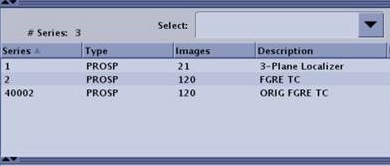

Image reconstruction considerations

- The Motion Compensation preview images are displayed in AutoView while scanning but they are not stored in the Patient List. When displayed in AutoView, the series number is multiplied by 100. For example, if the original series is 2, the preview series, as displayed in AutoView, is 200.

Figure 5. AutoView series

- For time course exams with Motion Compensation selected, the Save Original scan parameter is automatically selected. This results in non-Motion Compensation and non-filtered images to display in AutoView, thus providing immediate image quality feedback

- For T1 MAP exams, Motion Compensation is automatically selected; it cannot be turned off.

- If Save Original scan parameter is selected (turned On), then non-Motion Compensation and non-filtered images and Motion Compensation and filtered images are created.

- If Save Original scan parameter is de-selected (turned off), then Motion Compensation and filtered images are created.